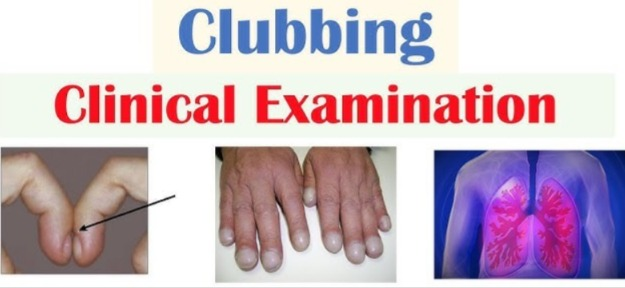

👉🏻 For your knowledge Clubbing of finger (ક્લબિંગ ઓફ ફિંગર):

- ક્લબિંગ ઓફ ફિંગરમાં નેઇલ એ એબનોર્મલ અને રાઉન્ડ શેપના (સ્પૂન જેવા) જોવા મળે છે.

- ક્લબિંગ ઓફ ફિંગર એ હાર્ટ અને લંગ ડિઝીસ માટેનું એક સાઇન છે જે ક્રોનિક Hypoxic કન્ડિશન ઇન્ડિકેટ કરે છે એટલે કે Body Tissues અથવા Organs માં ઓક્સિજનનું લો લેવલ દર્શાવે છે જેમ કે ક્રોનિક લંગ ઇન્ફેક્શન, ક્રોનિક લંગ મેલીગનન્સી

- ફિંગરમાં ક્લબિંગ પ્રેઝન્ટ છે કે નહીં તે ચેક કરવા માટે સ્કાર્મરોથ વિન્ડો ટેસ્ટ કરવામાં આવે છે.